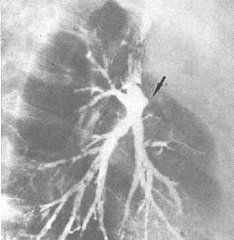

ABPA的特異性影像表現為以上葉為主的中心性支氣管擴張,CT掃描可見支氣管管壁增厚、管徑擴張和雙軌征、印戒征,由於分泌物痰栓阻塞支氣管可表現為條帶狀、分支狀或牙膏樣、指套樣陰影。黏液嵌塞也是ABPA常見、並有一定特徵性的X線徵象,有37%~65%患者在病程某一時間有黏液嵌塞的X線證據,占全部一過性病變的近1/3。典型表現為2~3cm長、5~8mm直條狀或指套狀分叉的不透光陰影從磨玻璃樣到實變影,以及因痰栓引起的肺不張等,晚期可出現肺氣腫和纖維化等。影像學改變以肺上葉改變更常見,為下葉的2~3倍。